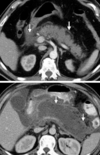

Chronic pancreatitis

54

58